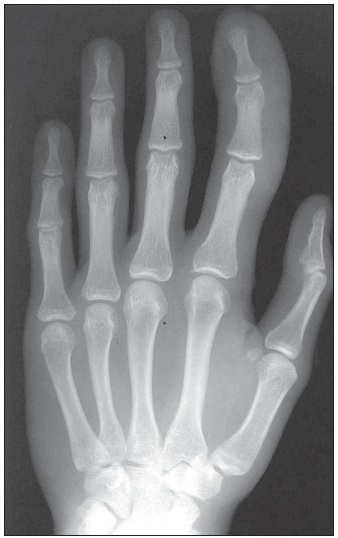

Photo Quiz: Can You Identify These Musculoskeletal Abnormalities?

04/29/2011

Douglas P. Beall, MD; John Whyte, MD, MPH

A 16-year-old boy is concerned that his right index finger looks "odd." The finger is several centimeters longer than his left index finger, and it is also wider.